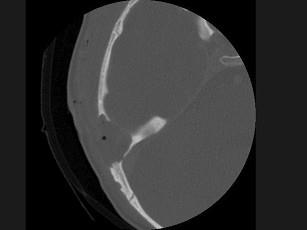

问题 女性,17岁,右耳乳突区隐痛,右耳后乳突区出现包块,逐渐增大,CT检查如图所示,请选择最可能的 ( )

选项 A、中耳癌 B、听神经瘤 C、化脓性中耳炎 D、嗜酸性肉芽肿 E、胆脂瘤

答案 D